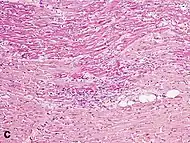

Micrograph of a myocardial infarction (ca. 400x H&E stain ) with prominent contraction band necrosis.

Histopathological examination of the heart may reveal infarction at autopsy. Under the microscope, myocardial infarction presents as a circumscribed area of ischemic, coagulative necrosis (cell death). On gross examination, the infarct is not identifiable within the first 12 hours.[20]

Although earlier changes can be discerned using electron microscopy, one of the earliest changes under a normal microscope are so-called wavy fibers.[21] Subsequently, the myocyte cytoplasm becomes more eosinophilic (pink) and the cells lose their transversal striations, with typical changes and eventually loss of the cell nucleus.[22] The interstitium at the margin of the infarcted area is initially infiltrated with neutrophils, then with lymphocytes and macrophages, who phagocytose ("eat") the myocyte debris. The necrotic area is surrounded and progressively invaded by granulation tissue, which will replace the infarct with a fibrous (collagenous) scar (which are typical steps in wound healing). The interstitial space (the space between cells outside of blood vessels) may be infiltrated with red blood cells.[20]

These features can be recognized in cases where the perfusion was not restored; reperfused infarcts can have other hallmarks, such as contraction band necrosis.[23]